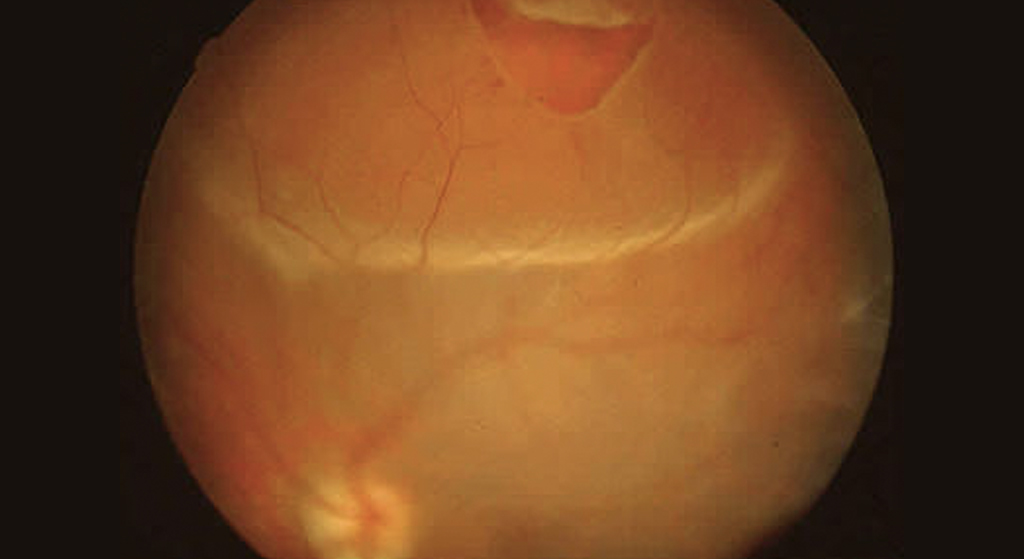

Desprendimiento de Retina

Consiste por la separación espontánea de la retina neurosensorial (capa interna de la retina) del epitelio pigmentado (capa externa) por un desgarro que no causa dolor y, en muchos casos, no va acompañado al inicio de pérdida de visión, por ello es importante estar alerta ante los síntomas de alarma como visión de moscas volantes, visión de destellos luminosos, distorsión de las imágenes, en el caso de experimentar la visión de una cortina negra que cae por alguna zona del campo visual, es señal de que ya existe un desprendimiento de retina, por lo que la consulta con un oftalmólogo debe ser inmediata.

Se produce por la separación espontánea de la retina neurosensorial (capa interna de la retina) del epitelio pigmentado (capa externa), a medida que envejecemos, el vítreo se encoge y tira la retina. Por lo general, el vítreo se separa de la retina sin ocasionar problemas, aunque a veces tira con demasiada fuerza y rompe la retina en uno o más lugares, lo que permite al liquido pasar a través de estos desgarros, separando la parte sensorial del epitelio pigmentado.